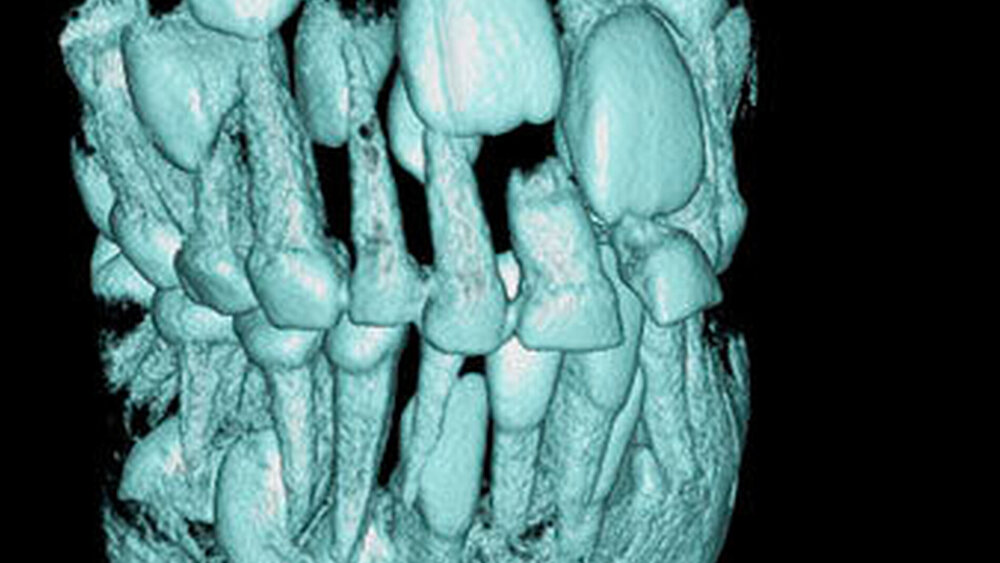

Überzählige Zähne können einzeln oder multipel auftreten [von Arx, 1990; Rajab Hamdan, 2002; Fernández Montenegro et al., 2006; Liu et al., 2007; Gündüz et al., 2008; Ferrés-Padró et al., 2009; Hyun et al., 2009]. Einzelne überzählige Zähne treten in 65,8 bis 80,5 Prozent, doppelte in 14,5 bis 27,7 Prozent und multiple in 0,6 bis 8 Prozent der Fälle auf [Rajab Hamdan, 2002; Fernández Montenegro et al., 2006; Liu et al., 2007; Ferrés-Padró et al., 2009; Hyun et al, 2009; Mossaz et al., 2014]. Einzelne oder doppelte überzählige Zähne finden sich typischerweise in der Oberkieferfront [Rajab Hamdan, 2002; Fernández Montenegroet al., 2006; Mossaz et al., 2014]. Multiple überzählige Zähne werden vor allem im Prämolarenbereich des Unterkiefers gefunden [Abbildung 4; YUSOF 1990, Ferrés-Padróet al., 2009; Wang Fan, 2011]. Multiple überzählige Zähne sind zudem oft mit anderen Erkrankungen oder Syndromen assoziiert, dazu gehören Lippen-Kiefer-Gaumenspalten, die cleidokraniale Dysplasie oder auch das Gardner-Syndrom. Bei Patienten mit einer Lippen-Kiefer-Gaumenspalte wird vermutet, dass sich die überzähligen Zähne aus der Fragmentierung der dentalen Lamina bei der Spaltbildung ergeben [Garvey et al., 1999; Wang Fan, 2011].